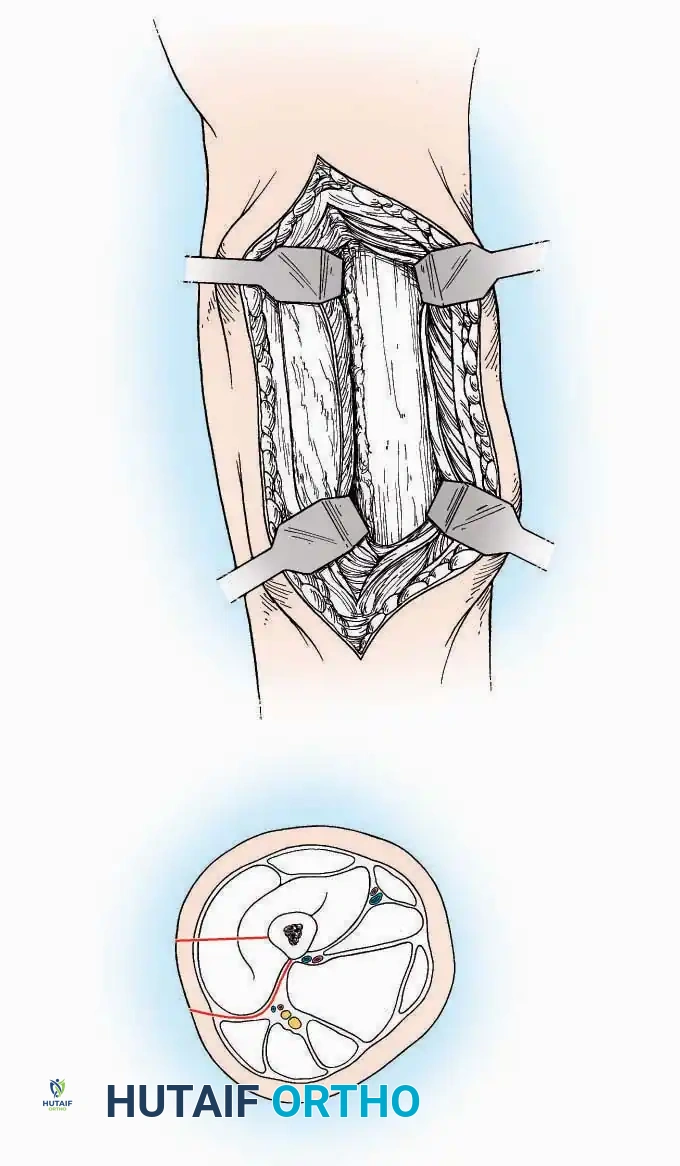

SURGICAL APPROACHES TO THE TARSUS AND ANKLE

Anterolateral Approach

The anterolateral approach is widely considered the "universal incision" for the foot and ankle. It provides unparalleled access to the ankle joint, the talus, and the majority of the tarsal articulations, while safely avoiding the major anterior neurovascular bundle. The only tarsal joints inaccessible via this route are the naviculocuneiform joints (specifically the medial and intermediate).

Indications: Total talectomy, triple arthrodesis, ankle arthrodesis, and open reduction of complex talar neck fractures.

Surgical Technique:

* Incision: Begin over the anterolateral aspect of the leg, medial to the fibula and 5 cm proximal to the ankle joint line. Carry it distally over the joint, crossing the anterolateral aspect of the talar body and the calcaneocuboid joint, terminating at the base of the fourth metatarsal.

* Superficial Dissection: Incise the superficial fascia and the superior and inferior extensor retinacula down to the periosteum of the tibia and the ankle joint capsule.

* Vascular Ligation: This trajectory usually requires the identification and ligation of the anterolateral malleolar and lateral tarsal arteries.

* Nerve Protection: Retract the skin edges carefully. Identify and protect the intermediate dorsal cutaneous branches of the superficial peroneal nerve (SPN), which frequently cross the distal aspect of this incision.

* Muscle Management: Identify the origin of the extensor digitorum brevis (EDB) muscle on the lateral calcaneus. Divide it in the direction of its fibers, or detach its origin entirely and reflect it distally to expose the subtalar and calcaneocuboid joints.

* Deep Exposure: Retract the extensor digitorum longus (EDL) tendons, the dorsalis pedis artery, and the deep peroneal nerve (DPN) medially. Incise the anterior ankle capsule to expose the tibiotalar joint.

* Tarsal Exposure: Expose the talonavicular joint by dissecting deep to the extensor tendons and incising its capsule transversely. Continue laterally through the capsule of the calcaneocuboid joint. By excising the fat pad within the sinus tarsi (lateral and inferior to the talar neck), the posterior facet of the subtalar joint is brought into direct view.

Anterior Approach

Indications: Total ankle arthroplasty (TAA), anterior ankle arthrodesis, and excision of anterior tibial/talar osteophytes (anterior impingement).

Surgical Technique:

* Incision: Make a 10 to 15 cm longitudinal incision over the anterior aspect of the ankle, centered exactly midway between the medial and lateral malleoli.

* Superficial Dissection: Incise the superficial fascia. Identify and protect the superficial peroneal nerve branches laterally and the saphenous nerve medially.

* Internervous Plane: The deep dissection exploits the plane between the Extensor Hallucis Longus (EHL) tendon (innervated by the deep peroneal nerve) and the Extensor Digitorum Longus (EDL) tendons (also innervated by the deep peroneal nerve).

* Neurovascular Bundle: Incise the extensor retinaculum. Carefully identify the anterior tibial artery and the deep peroneal nerve, which typically lie between the EHL and EDL, or directly deep to the EHL. Retract the neurovascular bundle laterally with the EDL, or medially with the EHL, depending on the specific anatomical variant encountered (lateral retraction is most common).

* Capsulotomy: Incise the anterior joint capsule longitudinally. Elevate the capsule subperiosteally from the anterior tibia and the talar neck to expose the entire tibiotalar articulation.